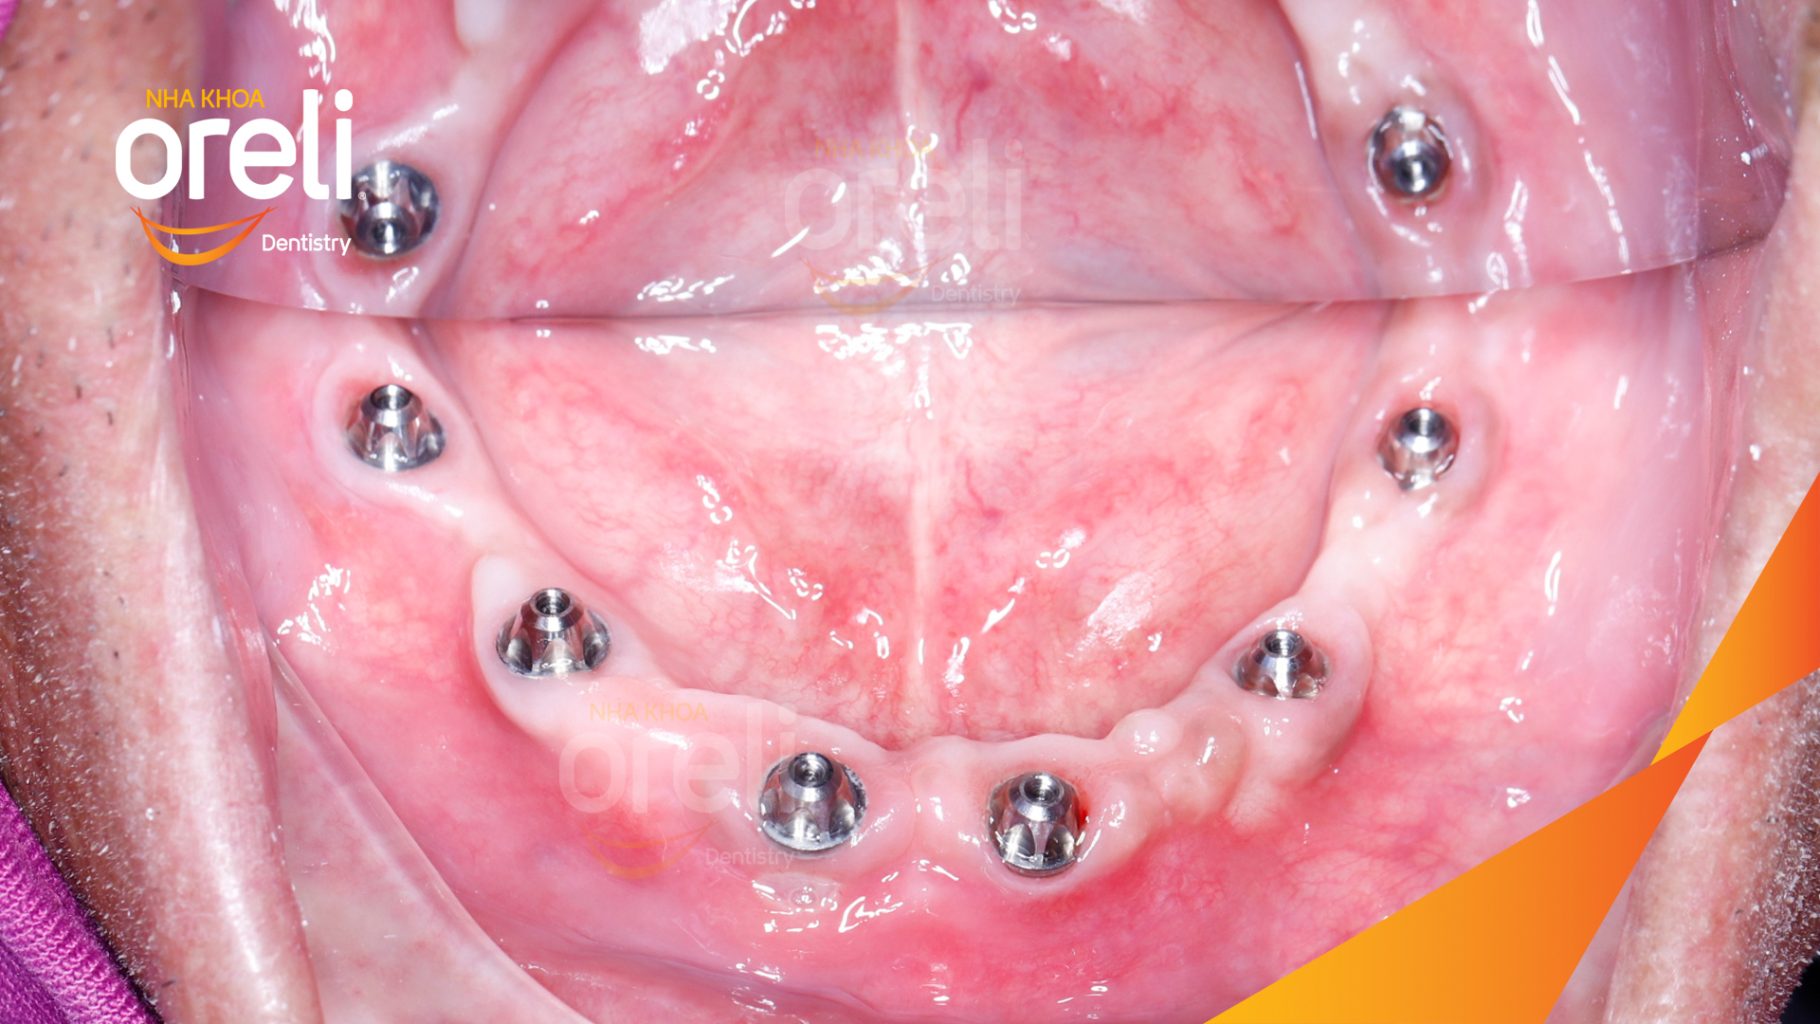

Tình trạng: Mất răng vùng răng sau hàm dưới, các răng trước lung lay mất khả năng hồi phục

Giải pháp: Nhổ răng trồng răng implant hàm dưới và hai răng hàm trên

Kết quả: Phục hồi vững chắc hàm dưới